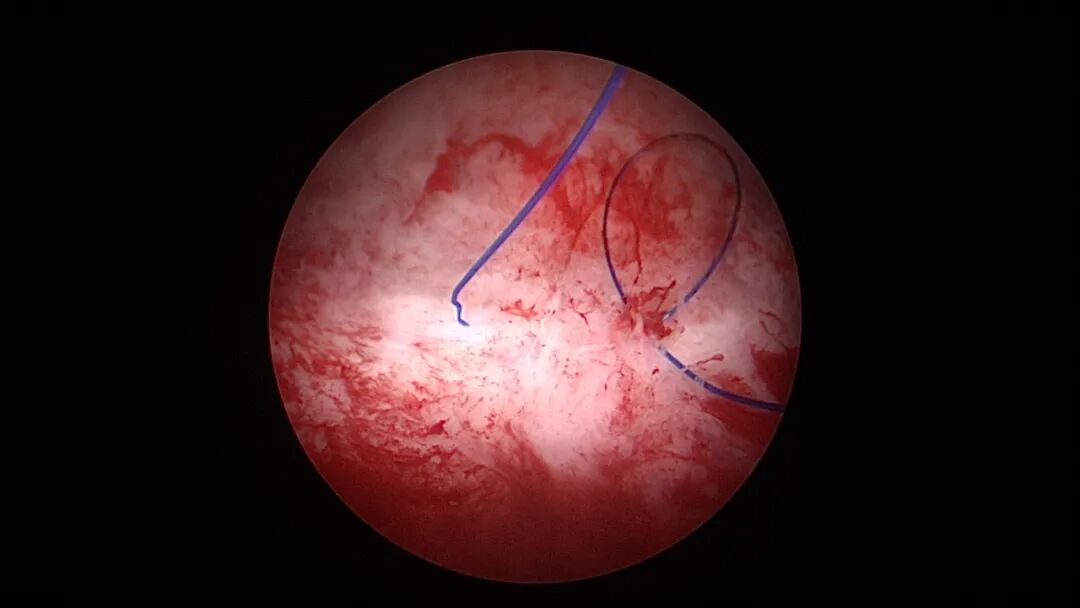

宫壁缝合2针线圈固定法:在宫壁缝合2针,线尾端固定节育环,距节育环0.5cm~1cm剪断线尾,将环送入宫腔,宫腔镜直视下整理并稍拉紧缝线,节育环被固定在缝合处。子宫肌层对静止的缝合线圈无法主动释放,形成节育环有效固定,宫颈外口剪断线尾,形成较长的线尾端。

取胚术后宫壁缝合2针线圈固定节育环图片及视频